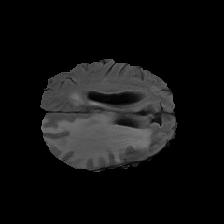

Brain tumor segmentation. Segmenting tumors in brain is challenging due to the high variance in appearance and shape of the tumors [28]. We use a subset of the 2017 Brain Tumour Image Segmentation (BraTS) dataset [29, 26]. It contains multi-parametric 3D MRI scans. The segmentation masks include (possibly overlapping) three classes of tumor. The 3D scans are split into 2D image slices, and only images that contain at least one tumor class are retained. Figure 7 shows three MSGNet generated samples as well as the corresponding masks. Since MSGNet adheres to the underlying relationships between various classes, we see that the generated images and the masks for different tumor classes are in line with the images and masks from the training set. In general, MSGNet rarely generated erroneous samples; we found roughly one sample per 3000 generations that could be rejected. Similar to the malaria experiment, we observed an improvement of 3.1% () in -score on the validation set.

A subset of the BrATS dataset was used. We used the images accompanied by segmentation layouts from the FLAIR and T1Gd modes. The segmentation layouts showed the sub-regions for three different classes: GD-enhancing tumor, the peritumoral edema, and the necrotic and non-enhancing tumor core. The brain and the background were treated as an additional class. We refer to [32] for further details. For the two modes, the background has been modelled using two different classes. We only considered half of the 155 slices, i.e., we took only the even-numbered slices and out of those we discarded the slices that did not include one of the previously mentioned tumor-classes in order to create a more balanced dataset. This resulted in 20,000 images that were further augmented with 6,000 MSGNet generated images. Example generations of the masks as well as the images are shown in Figure 12.